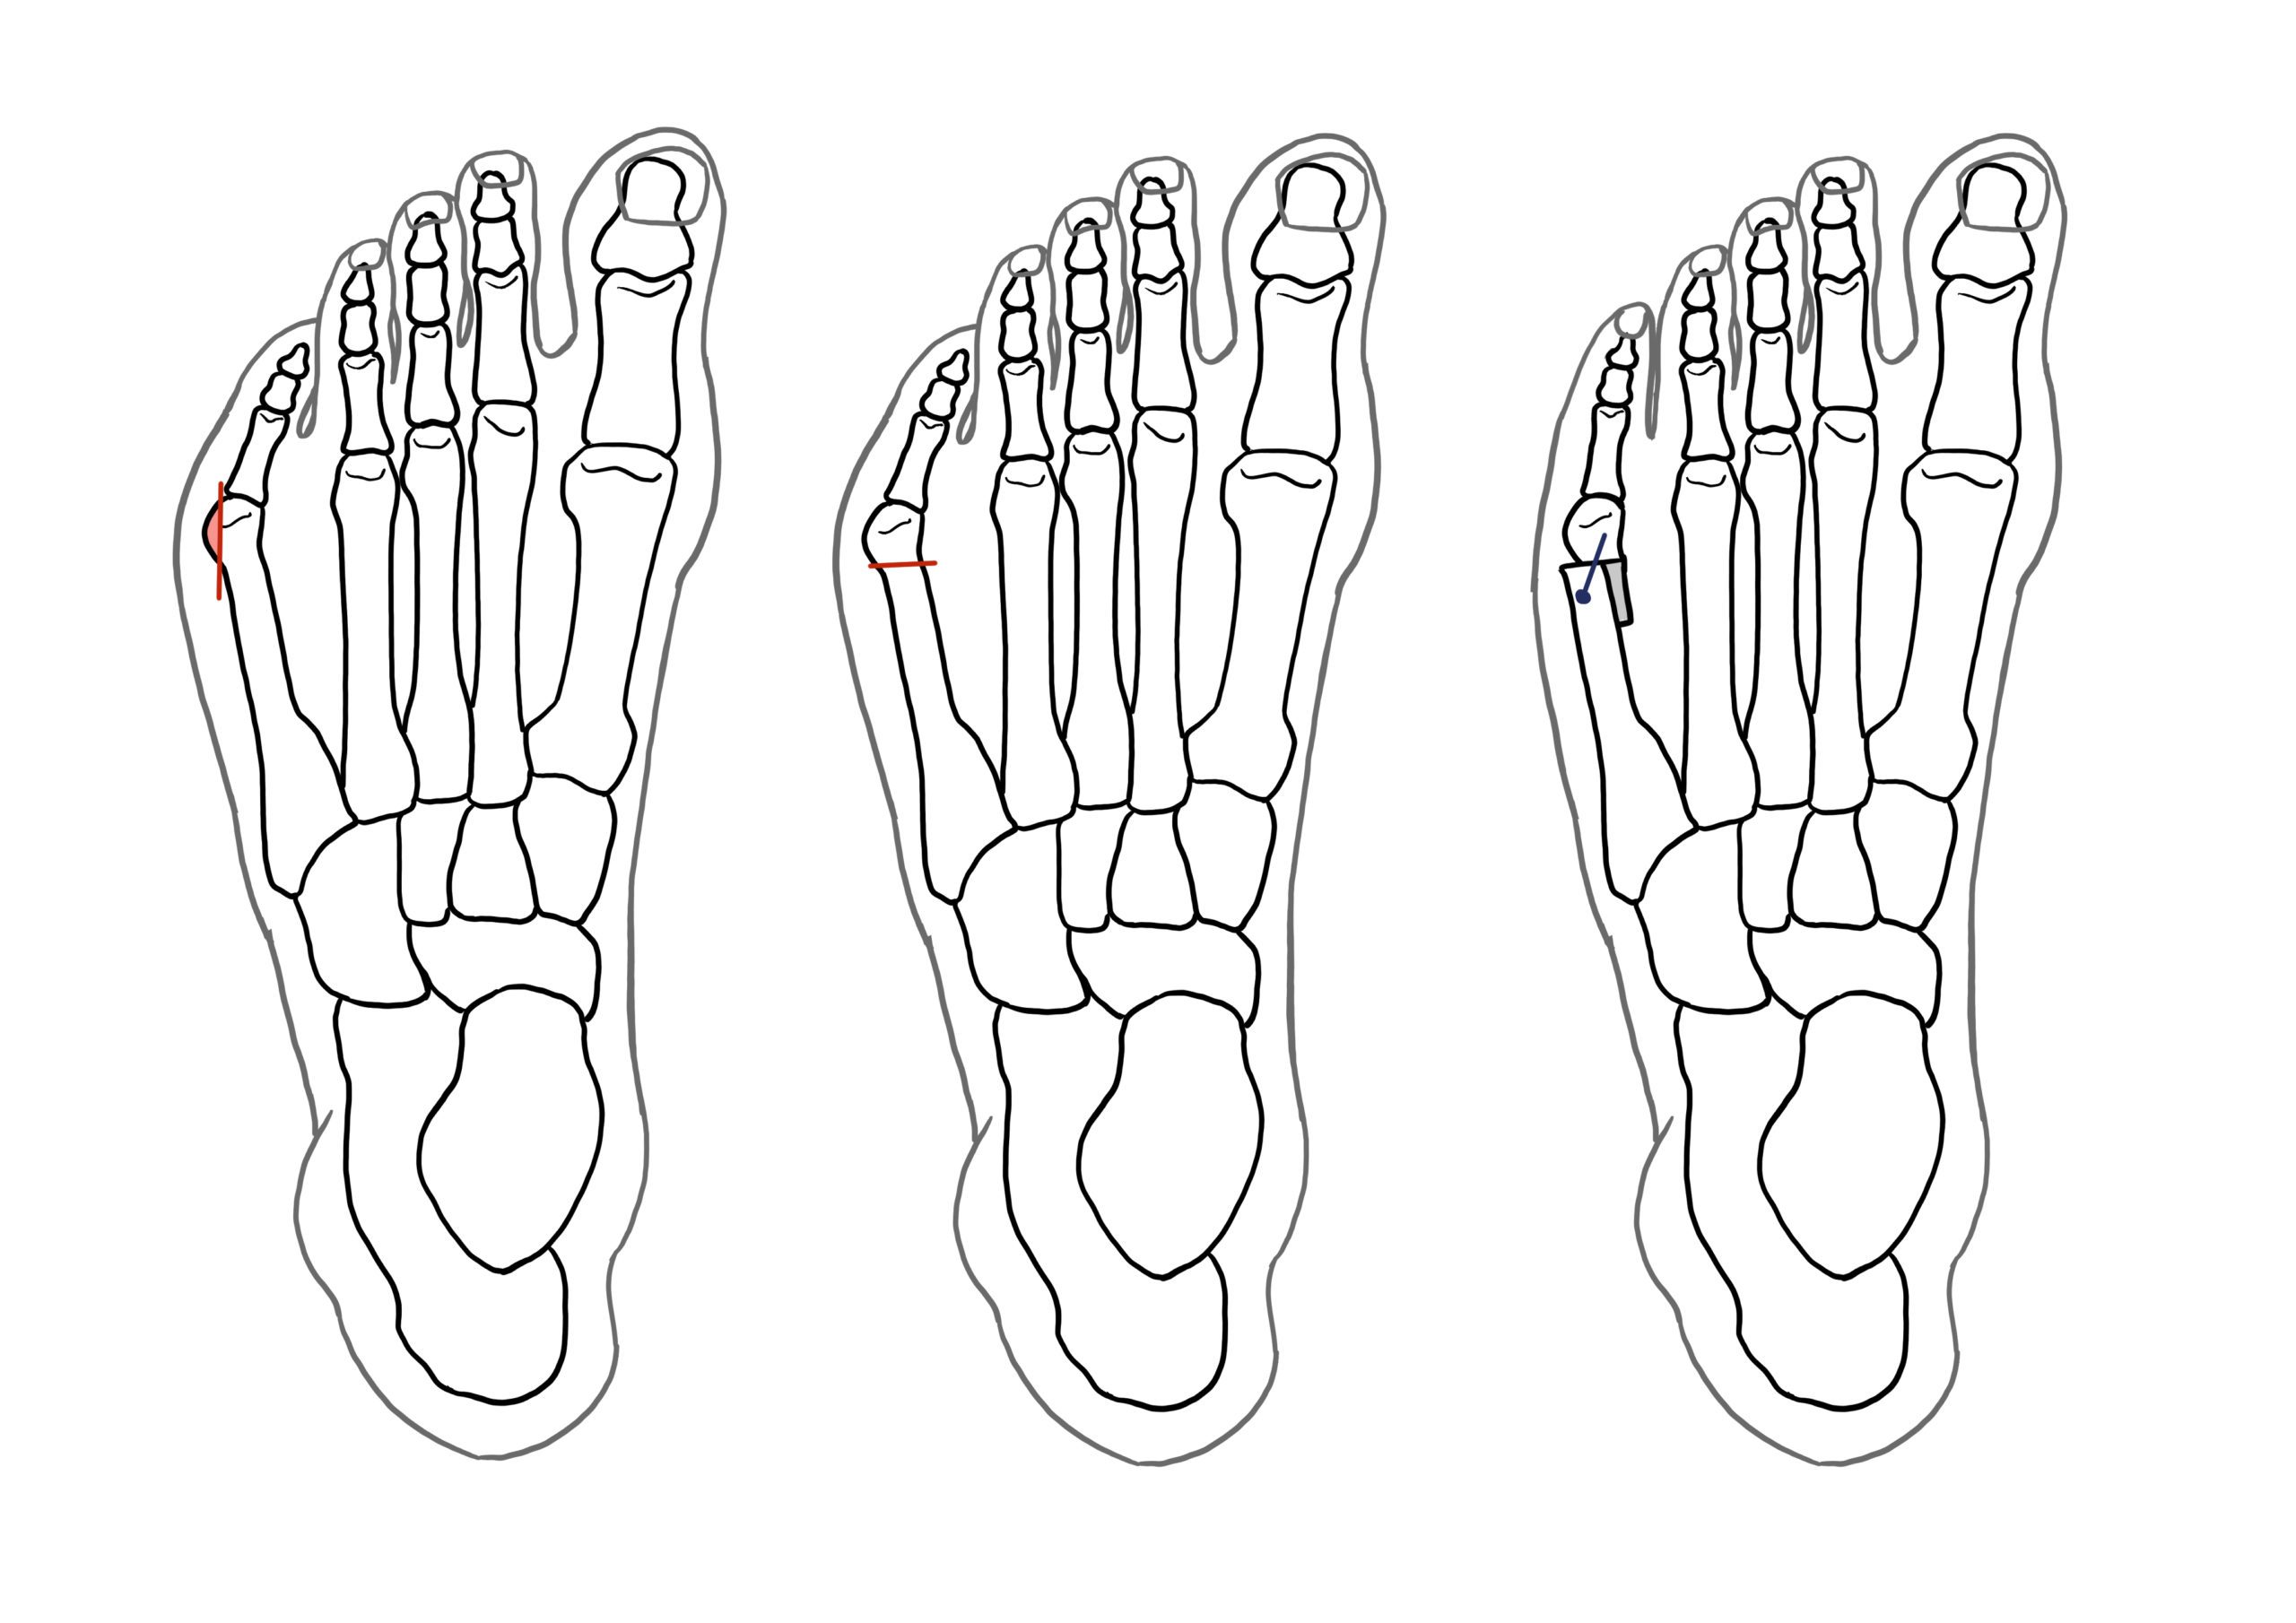

Tailor's Bunion Surgery A Complete Guide Foot & Ankle

Tailor's Bunion Surgery A Complete Guide Foot & Ankle What Age Can You Get Bunion Surgery For optimum results, bunion surgery should be done between the ages of 18 and 60. An orthopaedic surgeon shares what to do before considering surgery. What is the best age for bunion surgery? learn about what a bunion is, reasons for surgery, the different types of bunion surgery and risks, and what to expect before,. bunion surgery (bunionectomy). What Age Can You Get Bunion Surgery.